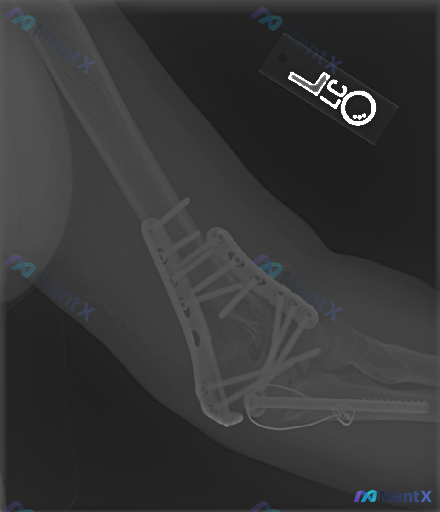

整理了一份左肘关节的病例资料,先抛出来大家一起看看。 基本背景: 左肱骨远端+尺骨鹰嘴骨折切开复位内固定术后,复查侧位X光。 影像报告给出的常规描述: - 肱骨远端双钢板、尺骨鹰嘴张力带钢丝+长螺钉固定,位置尚可 - 骨折对位可,关节关系维持,未见明显脱位/半脱位 - 未见明显内固定断裂、松动征象...

整理到一组左侧肘关节(标注为L)的侧位X光片影像资料,结合读片分析,核心发现如下: - 骨结构:尺骨近端(靠近肘关节处)可见骨皮质中断,有明显斜行骨折线伴移位、成角;肱骨远端干骺端也可见皮质中断;桡骨近端未见明确皮质中断。 - 关节关系:肘关节正常解剖结构破坏,肱骨、尺骨、桡骨之间的关节匹配关系明显...

整理到一份影像读片资料,觉得很适合讨论临床思维里的“小陷阱”。 先不说结论,只看原始情境:有人拿到这张影像,第一定位错了,后面的分析全偏了。再仔细看,还有个更大的问题——金属伪影把关键区域挡住了,看似“没明显异常”,其实什么都没法确定。 大家觉得: 1. 拿到这类带内固定的复查片,第一步最应该先确认...